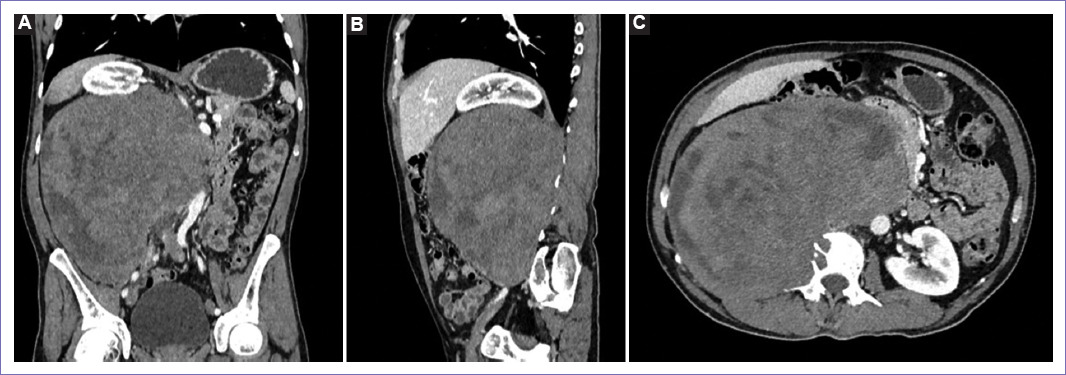

Figura 1 Tomografía espiral multicorte de abdomen y pelvis al ingreso. A: en vista coronal se observa una tumoración de aspecto neoproliferativo a nivel retroperitoneal derecho, de densidad heterogénea con áreas hipodensas (sugiere necrosis), mide 17 x 17 x 12 cm y presenta captación heterogénea del contraste. B: en vista sagital se observa el desplazamiento craneal del riñón derecho, por la masa retroperitoneal anterior a la vena cava inferior. C: en vista sagital se observa el efecto lítico a nivel de cuerpo vertebral de L2 y mala interfase con músculo psoas.

Figura 4 Tomografía espiral multicorte de abdomen y pelvis a los cinco meses. A: masa sólida en el lado derecho del retroperitoneo, muestra captación heterogénea de la sustancia de contraste, mide 21 x 22 x 15 cm, ejerce efecto de masa desplazando hacia cefálico el hilio y riñón derecho, sin evidencia de infiltrarlo, así mismo desplaza el uréter hacia ventral en todo su trayecto; desplaza hacia contralateral la aorta abdominal, páncreas y asas delgadas, contacta la unión de la venas ilíacas. B: el trayecto de la vena cava inferior no se logra representar adecuadamente, por la infiltración de la masa retroperitoneal. C: masa que infiltra el músculo psoas, así como el cuerpo vertebral L2, condicionando lesiones líticas, además se extiende hacia el neuroforamen L2-L3 derecho.